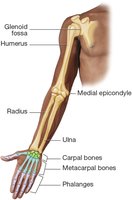

Upper Extremity

Humerus: Upper arm bone

Radius and Ulna: Forearm bones

Carpals: Eight wrist bones

Metacarpals: Five hand bones

Phalanges: Finger bones (three per finger, two in thumb)